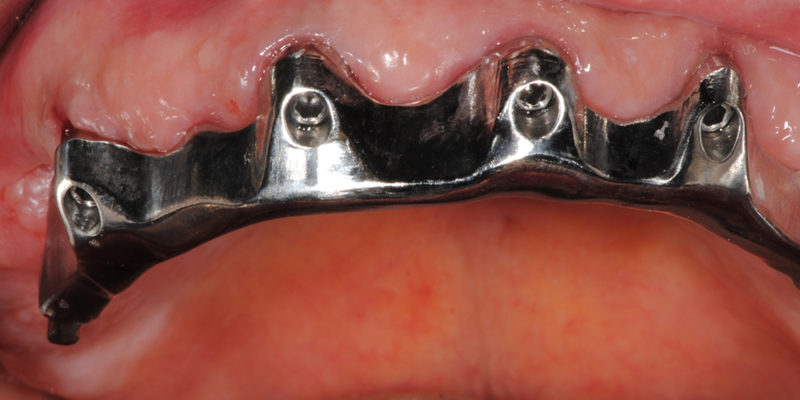

Ripristino dell’arcata superiore su overdenture su barra